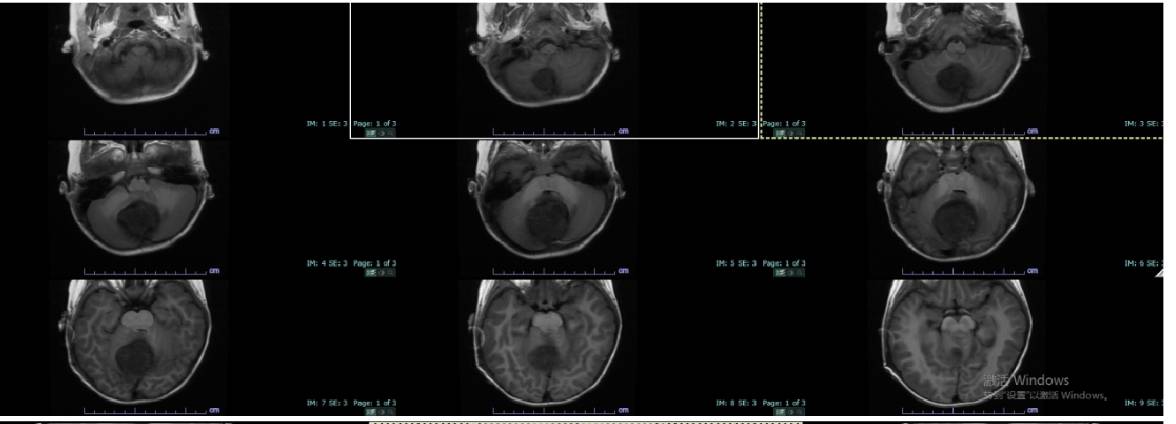

王冬冬 , 3岁 , 在1个月前无明显诱因突然意识丧失 , 肢体抽搐 , 口吐白沫并伴有恶心、剧烈呕吐 。 在当地医院做CT检查发现脑部明显积水 , 脑干背侧占位 , 进一步核磁共振检查发现脑干区实性占位 , 当地医院不敢做 , 说只有北京能做这样的手术 。

后听人说郑大三附院小儿神经外科主任杨继学会作这样的手术 , 于是便驱车几百公里来求医 , 杨主任仔细查看患者头颅磁共振 , 发现患者脑干区被肿瘤压迫严重 , 手术难度非常大 , 风险性极高 , 杨主任立即和马云富主任商量治疗方案 , 经过详细的术前讨论 , 制定缜密的手术方案 , 详细告知家属病情及手术方案 , 经过完善的术前准备 , 在杨继学主任及马云富主任联合相关科室最终完成这例显微镜下脑干区肿瘤切除手术 , 术后患者恢复良好 , 无神经功能障碍 , 术后病理诊断为:卵黄囊瘤 , 术后患儿行放化疗 。 该位置卵黄囊瘤在儿童中极其少见 , 是一种高度恶性肿瘤 。